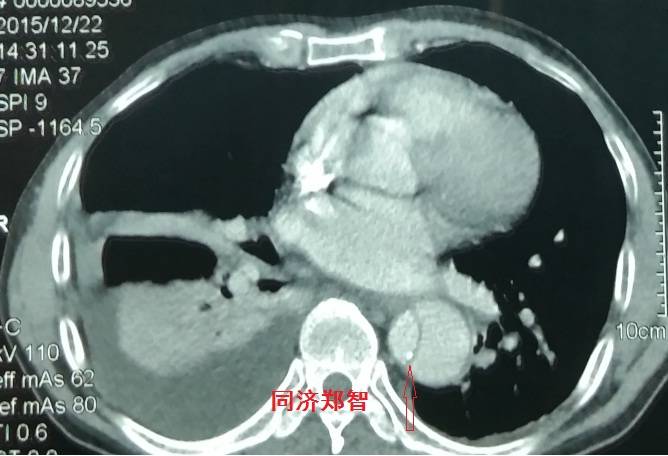

病例十

腹主动脉平扫CT提示正常外周一圈的钙化影中有内移的钙化影(红色箭头所示),CTA 证实为腹主动脉夹层